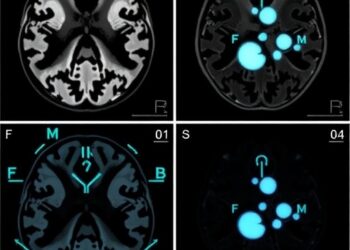

In a groundbreaking study published in Pediatric Radiology, researchers conducted a meticulous examination of fetal brain development through advanced multi-centric ...